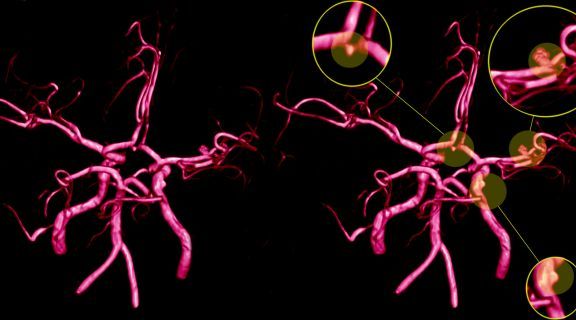

Em muitos casos, identificar um aneurisma antes do rompimento pode permitir um acompanhamento mais seguro e a definição do melhor momento para intervir. Para pessoas com fatores de risco, exames de imagem ajudam a mapear os vasos cerebrais e avaliar possíveis alterações.

Com o avanço da tecnologia, tratamentos minimamente invasivos podem ser indicados, permitindo acessar o aneurisma por dentro dos vasos e reduzir riscos. Essas abordagens tendem a oferecer mais precisão, menor impacto ao organismo e uma recuperação mais rápida.